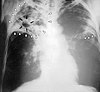

ଯକ୍ଷ୍ମା (ଟିବି) ଏକ ସଂକ୍ରମକ ରୋଗ ଯାହା ମାଇକୋବ୍ୟାକ୍ଟେରମ ଟ୍ୟୁବରକ୍ୟୁଲୋସିସଦ୍ୱାରା (MTB) ହୁଏ । ଯକ୍ଷ୍ମା ସାଧାରଣତଃ ଫୁସଫୁସକୁ ଆକ୍ରମଣ କଲେ ମଧ୍ୟ ଶରୀରର ଯେ କୌଣସି ଅଙ୍ଗରେ ଏହାଦ୍ୱାରା ରୋଗ ହୋଇପାରେ । ଅଧିକାଂଶ ସଂକ୍ରମଣରେ କୌଣସି ଲକ୍ଷଣ ହେଉ ନଥିବାରୁ ତାହାକୁ ପ୍ରଛନ୍ନ ଯକ୍ଷ୍ମା ଓ ଇଂରାଜୀ ଭାଷାରେ ଲେଟେଣ୍ଟ ଟ୍ୟୁବରକୁଲୋସିସ (latent tuberculosis) କୁହାଯାଏ । ଏହି ପ୍ରଛନ୍ନ ଯକ୍ଷ୍ମା ମଧ୍ୟରୁ ପ୍ରାୟ ୧୦% ସଂକ୍ରମଣ ସକ୍ରିୟ ରୋଗରେ ପରିଣତ ହୁଏ ଯାହାକୁ ଚିକିତ୍ସା ନ କଲେ ସେଥିରୁ ଅଧେ ଲୋକ ମୃତ୍ୟୁ ବରଣ କରନ୍ତି । ସକ୍ରିୟ ଫୁସଫୁସ ଯକ୍ଷ୍ମା ରୋଗରେ କ୍ରନିକ ବା ଦୀର୍ଘକାଳୀନ କାଶ ସହିତ ରକ୍ତ ମିଶ୍ରିତ ଖଙ୍କାର ପଡ଼େ, ଜ୍ୱର, ରାତ୍ରୀ ସ୍ୱେଦ ନିର୍ଗତ ଓ ଓଜନ ହ୍ରାସ ହୁଏ । ଓଜନ ହ୍ରାସ ହେଉଥିବାରୁ ଏହାକୁ କ୍ଷୟ ରୋଗ ନାମ ଦିଆଯାଇଥିଲା । ବିଭିନ୍ନ ଅଙ୍ଗର ସଂକ୍ରମଣରେ ଭିନ୍ନ ଭିନ୍ନ ପ୍ରକାର ଲକ୍ଷଣ ପ୍ରକାଶ ପାଏ ।